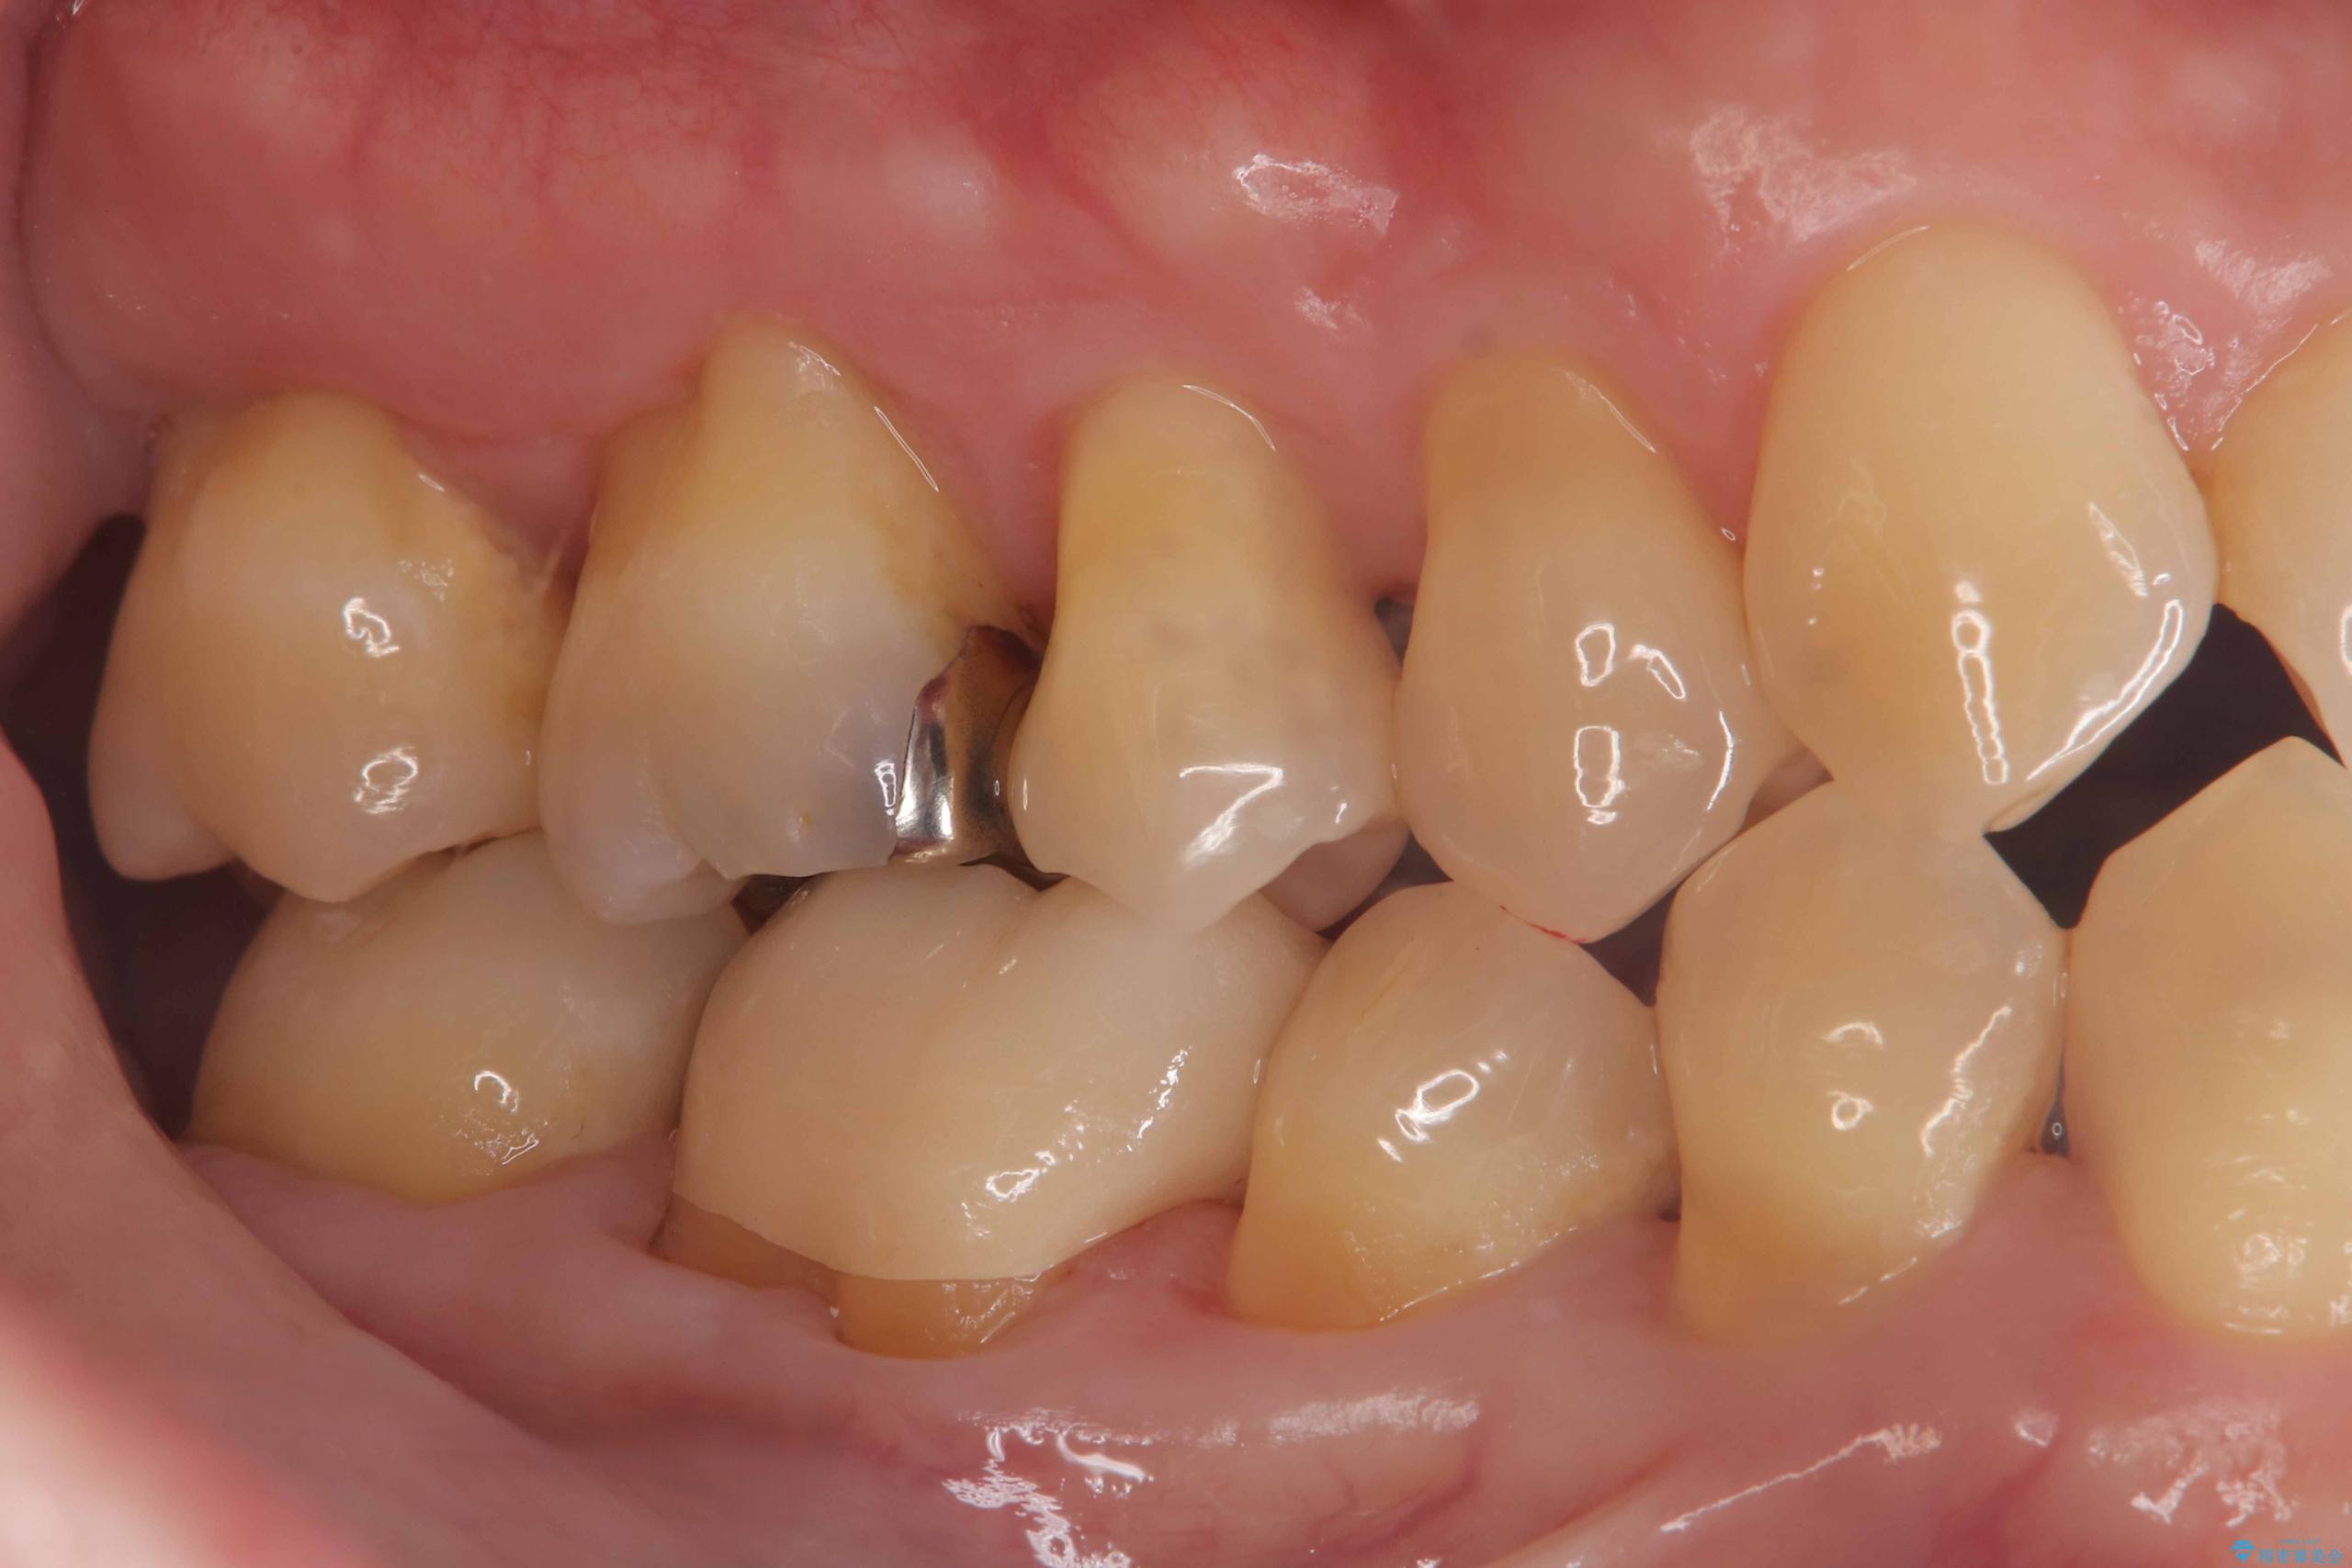

- 「銀歯を白くしたい」を主訴に来院された患者様です。銀歯を外し虫歯を除去後、オールセラミッククラウンで治療を行いました。

銀歯を外して内部の虫歯を丁寧に除去した後、オールセラミッククラウンにて修復を行いました。審美性と機能性の両面で改善が得られ、患者様にもご満足いただきました。